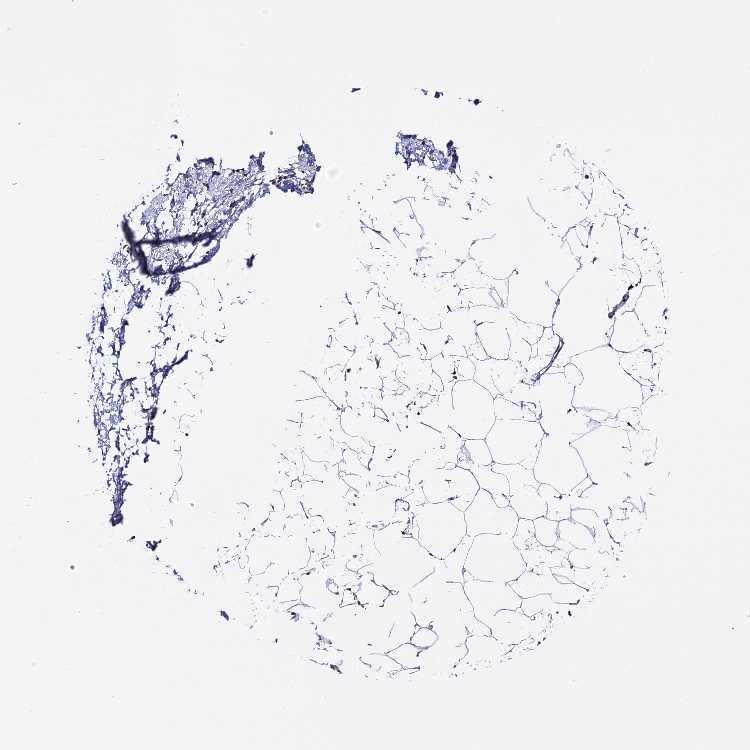

TISSUE PRIMARY DATA SOFT TISSUE Show tissue menu

SOFT TISSUE 1 - Antibody stainingi

Antibody staining in the annotated cell types in the current human tissue is reported as not detected, low, medium, or high, based on conventional immunohistochemistry profiling in selected tissues. This score is based on the combination of the staining intensity and fraction of stained cells.

Each image is clickable and will lead to virtual microscopy that enables deeper exploration of all samples and also displays staining intensity scores, fraction scores and subcellular localization as well as patient and tissue information for each sample.

Antibody HPA035865Antibody HPA041189

Chondrocytes Low-

Fibroblasts Not detectedMedium

Peripheral nerve Not detectedMedium

SOFT TISSUE 2 - Antibody stainingi

Chondrocytes LowMedium

Peripheral nerve -Medium